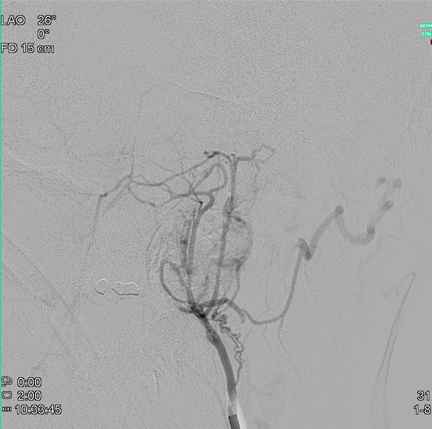

Die präoperative Embolisation eines gefäßreichen Tumors dient zur Verminderung des operativen Blutungsrisikos. in der Regel lassen sich hierdurch ca. 90% des Tumors von der Gefäßversorgung abhängen.

Hierzu wird ähnlich wie bei der diagnostischen Angiographie ein Zugang über die Leistenschlagader gewählt und dann die tumorversorgenden Gefäße mit einem Mikrokatheter sondiert. In der Regel wird das Gefäßbett des Tumors mittels kleiner Partikel emboliiert, ggf. auch mit einem Gefäßkleber.

Der Eingriff dauert ca. 45-60min, hierfür ist keine Vollnarkose notwendig.